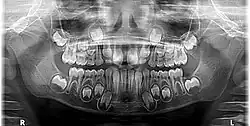

En la dentición temporal hay 20 dientes en total: 8 incisivos, 4 caninos y 8 molares temporales.

Caída y extracción